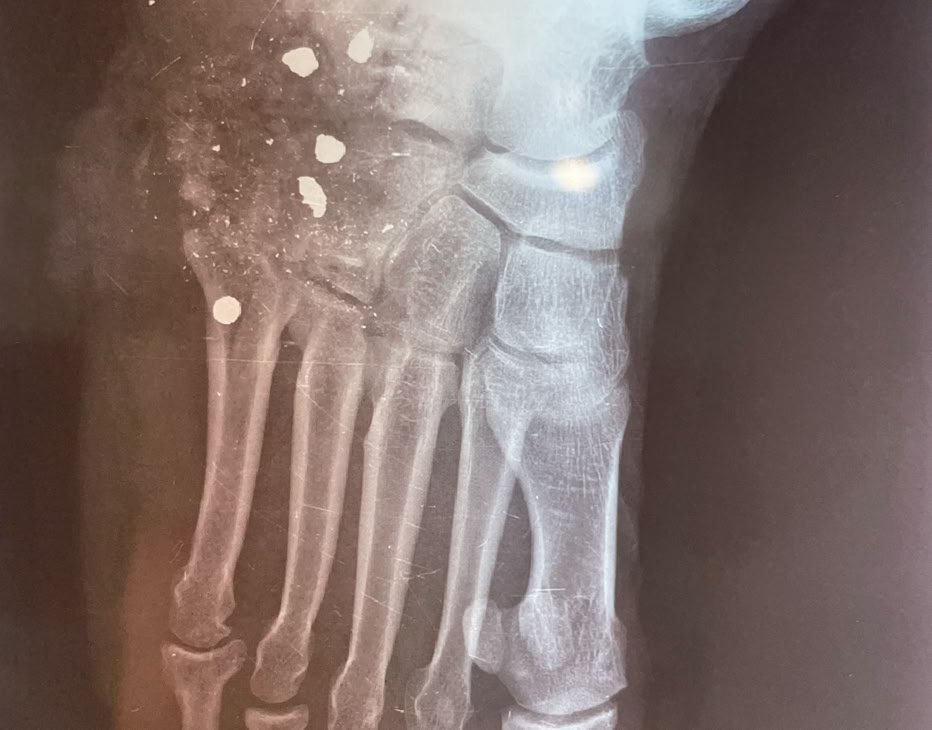

Nada más llegar, pase de visita para ver como empezar a programar las intervenciones de la semana. No había muchos pacientes ingresados pendientes de cirugía, pero no tuvimos que esperar mucho rato para recibir una herida por arma de fuego en un pie y una fractura de cadera de un paciente trasladado de un hospital de los Hermanos de San Juan De Dios que tratan enfermos de Lepra.

Ambos se resolvieron el lunes por la mañana con una prótesis parcial de cadera y el disparo en el pie con una cirugía de desbridamiento, limpieza y cierre.

Como siempre, el trabajo no falta y hemos atendido diversas urgencias. Sirva como ejemplo el clásico “PANADIZO CAMERUNÉS” y las fracturas abiertas de tibia.

Aquí presentamos un par de estos casos, consecuencia la mayoría de las veces por tratar fracturas complejas con masajes y acudir a nosotros muchos meses después.